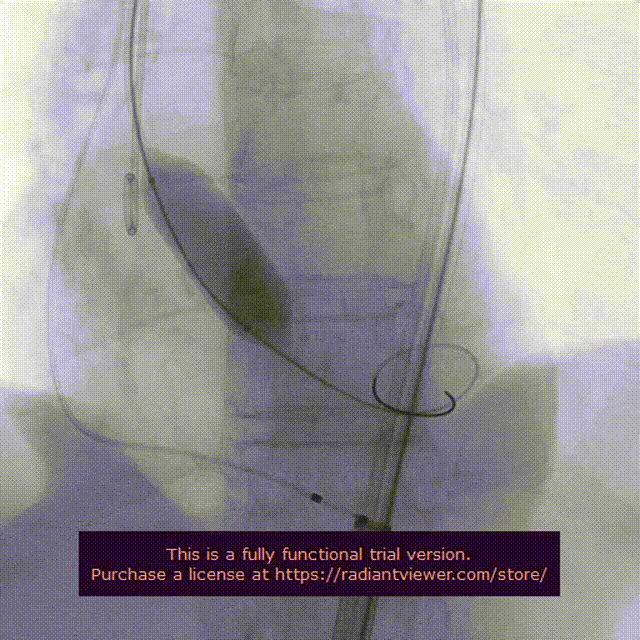

右颈置入保护伞

左颈置入保护伞